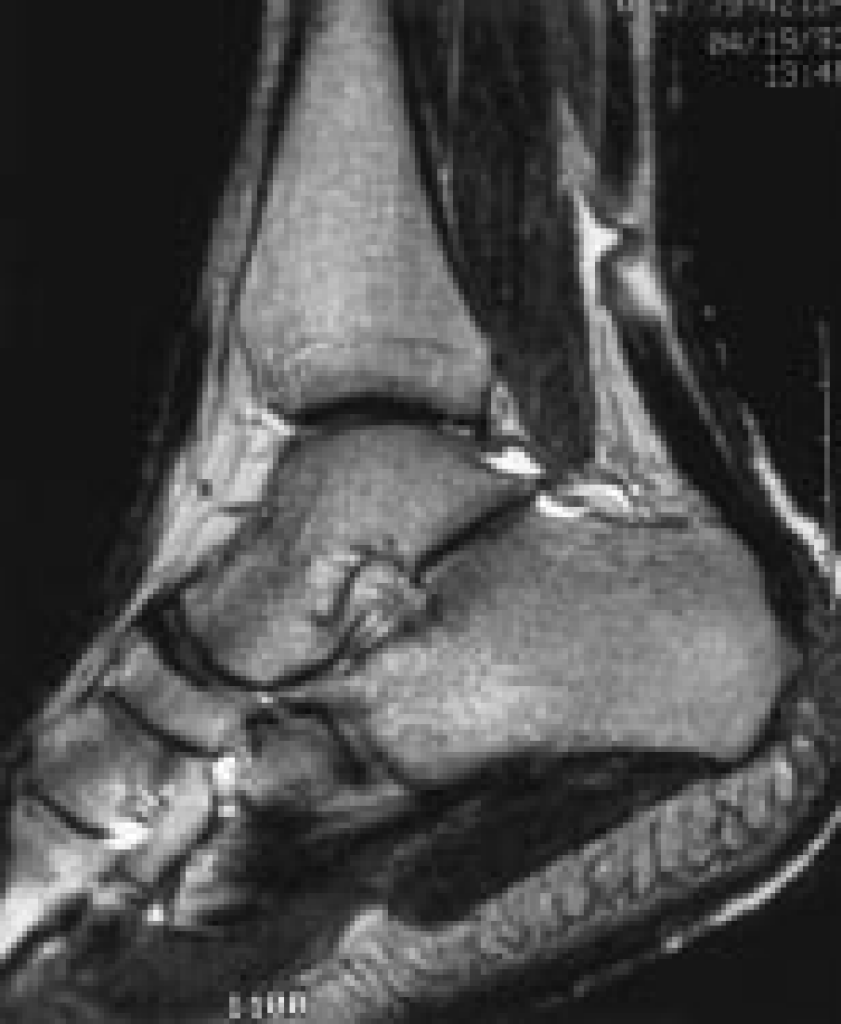

Acute Achilles’ Tendon Rupture

Rupture of the Achilles’ tendon may follow a period of pain prior to rupture. The actual inciting event however, is usually mechanical stress with a rapid loading of an already-tensed tendon, e.g. lunging forward from a standing start, unexpected stepping in a hole, or jumping from a height. Whatever the cause, patients often describe a sudden pain likened to being kicked in the back of the ankle/lower leg, which may be accompanied by an audible pop.

An operation involves an incision at the back of the leg, and the 2 tendon ends are sewn back together. Very occasionally a strong direct repair is not possible due to significant damage in the tendon upon rupture. In this situation, a spare tendon in the back of the leg or hamstring tendon may be required to augment the repair.